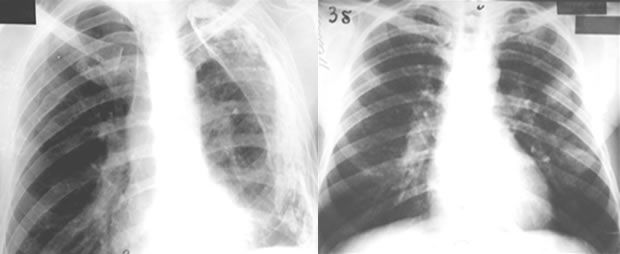

RADIOLOŠKI NALAZ

- PRI MANJEM PROCENTU SiO2 U RUDI: Pojačan i deformisan plućni crtež u srednjim i gornjim plućnim poljima.

- PRI VEĆEM PROCENTU SiO2 U RUDI: Punktiformna, nodularna i mikronodularna zasjenčenja. Pleuralna zadebljanja i adhezije